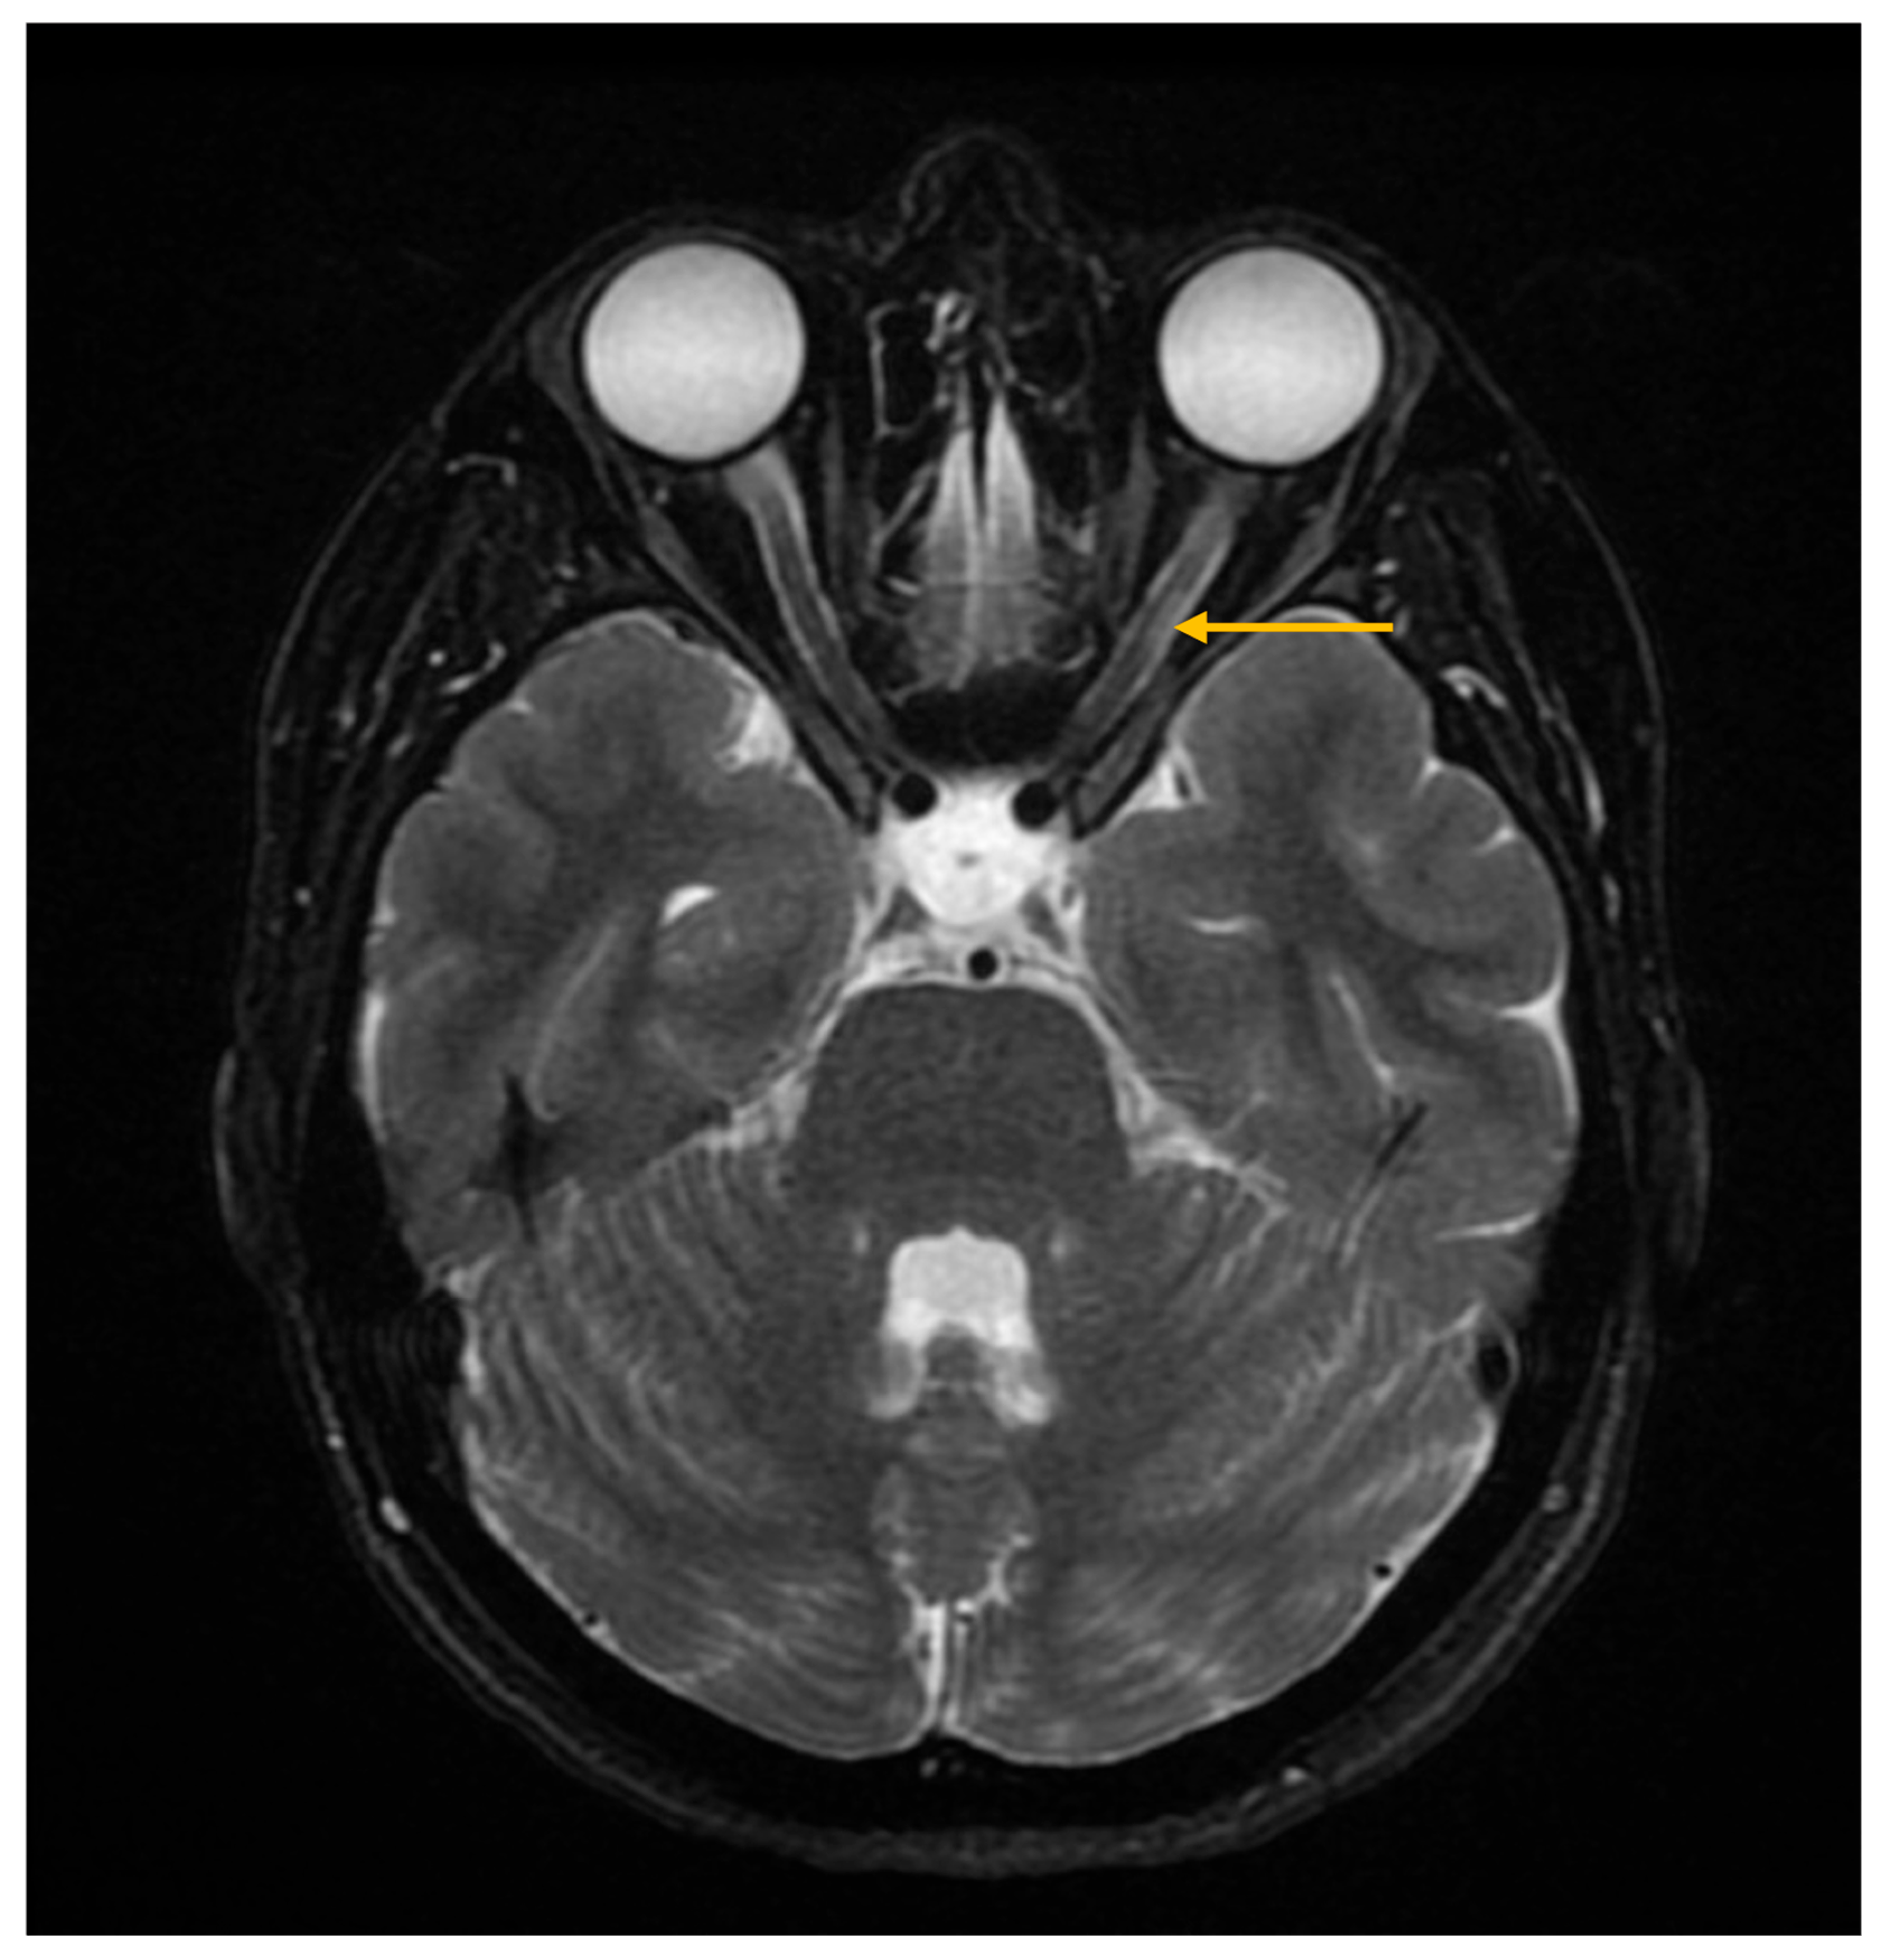

Central nervous system involvement is reported in approximately 10.8% of patients with Sjögren’s syndrome, manifesting as headache, as well as sensory–motor syndromes and visual disturbances [25,51]. Magnetic resonance imaging plays an essential role in detecting structural changes within the central nervous system in the context of Sjögren’s syndrome [16,52].

In patients with Sjögren’s syndrome and neurological involvement, MRI may reveal cerebral demyelinating lesions with a distribution and appearance similar to those observed in multiple sclerosis (Figure 6) [25]. However, the published data regarding their significance are contradictory; some studies report a higher prevalence of demyelinating changes in Sjögren’s syndrome compared with control groups, while others do not demonstrate significant differences, suggesting that these lesions may instead reflect changes associated with normal physiological aging [53,54].

In some patients with Sjögren’s syndrome and neurological manifestations, MRI may reveal lesions with features characteristic of neuromyelitis optica or disorders within the neuromyelitis optica spectrum, suggesting a possible association between the conditions (Figure 7) [16,25,52].

Figure 7. Magnetic resonance imaging (MRI) of the brain and orbits, axial T2-weighted short tau inversion recovery (STIR) sequence. The image demonstrates hyperintensity of the left optic nerve (arrow), consistent with optic neuritis.